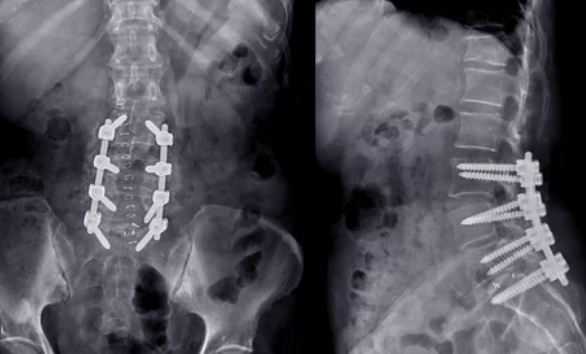

중요한 것은 적절한 진단을 받는 것입니다. 의사는 환자의 증상을 평가하고 MRI나 CT 스캔과 같은 영상 진단을 통해 허리디스크의 정도를 확인할 수 있습니다. 이를 통해 가장 적합한 치료 방법을 결정할 수 있습니다.

만약 보존적 치료로 충분한 개선이 이루어지지 않는 경우, 수술적 치료를 고려할 수 있습니다. 수술은 디스크의 일부 또는 전체를 제거하고 척추를 안정화시키는 방법을 포함할 수 있으며, 심각한 경우에만 선택됩니다.

허리디스크, 또는 요추 추간판 탈출증은 척추의 디스크가 손상되어 신경을 압박하며 통증을 유발하는 질환입니다. 이 질환의 치료 방법 중 하나는 수술이며, 수술은 증상의 심각성과 환자의 상태에 따라 결정됩니다. 허리디스크 수술은 다양한 방법으로 시행되며, 각각의 방법은 비용이 상이합니다.

수술을 고려하는 환자들에게는 비용이 중요한 고려 사항 중 하나입니다. 일반적으로, 허리디스크 수술비용은 수술의 종류, 병원의 위치, 의료진의 전문성, 그리고 수술에 필요한 장비와 기술에 따라 달라집니다. 예를 들어, 전통적인 개방 수술은 비용이 상대적으로 낮을 수 있으나, 미세 현미경을 사용하는 수술이나 인공디스크 치환술과 같은 더 복잡한 수술은 더 높은 비용이 발생할 수 있습니다.

허리디스크 수술의 비용은 대략적으로 신경차단술의 경우 회당 10만원 내외, 신경성형술과 수핵성형술은 200만원대, 내시경 레이저 시술은 300만원대, 허리디스크 절제 수술은 150~200만원대, 미세 현미경 제거 수술은 300~500만원대, 척추고정 유합 수술은 700만원대, 인공디스크 치환술은 700~1000만원대로 다양합니다.